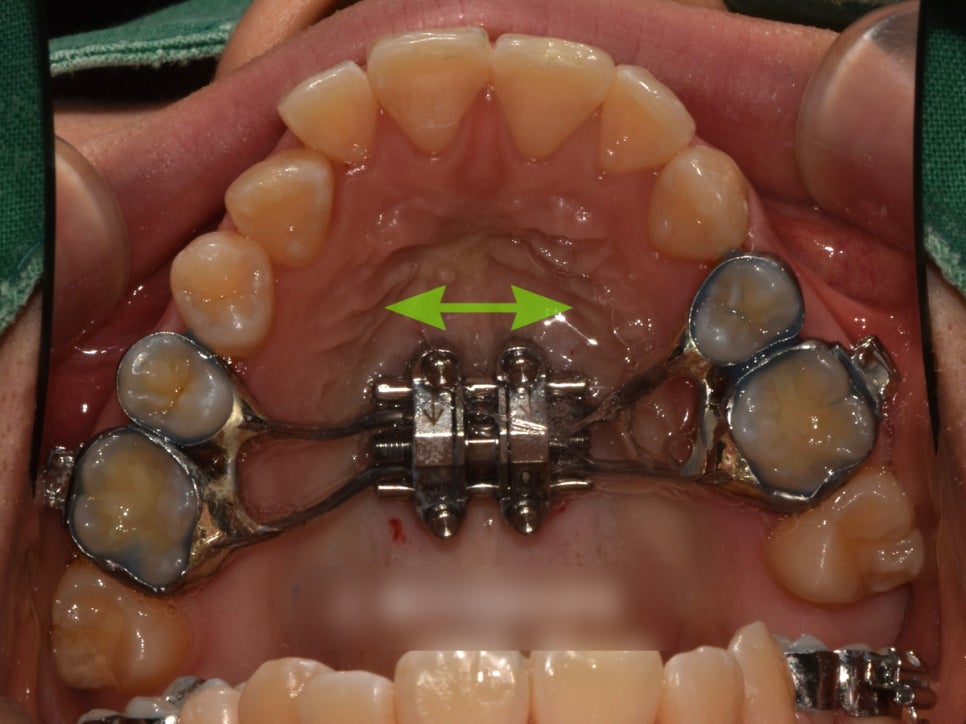

점점 긴밀해져가는

교합의 변화를 확인할 수 있습니다.

가장 중요한 양쪽 어금니 교합이

잘 물리는 상태로 양호하게

마무리 된 모습입니다.